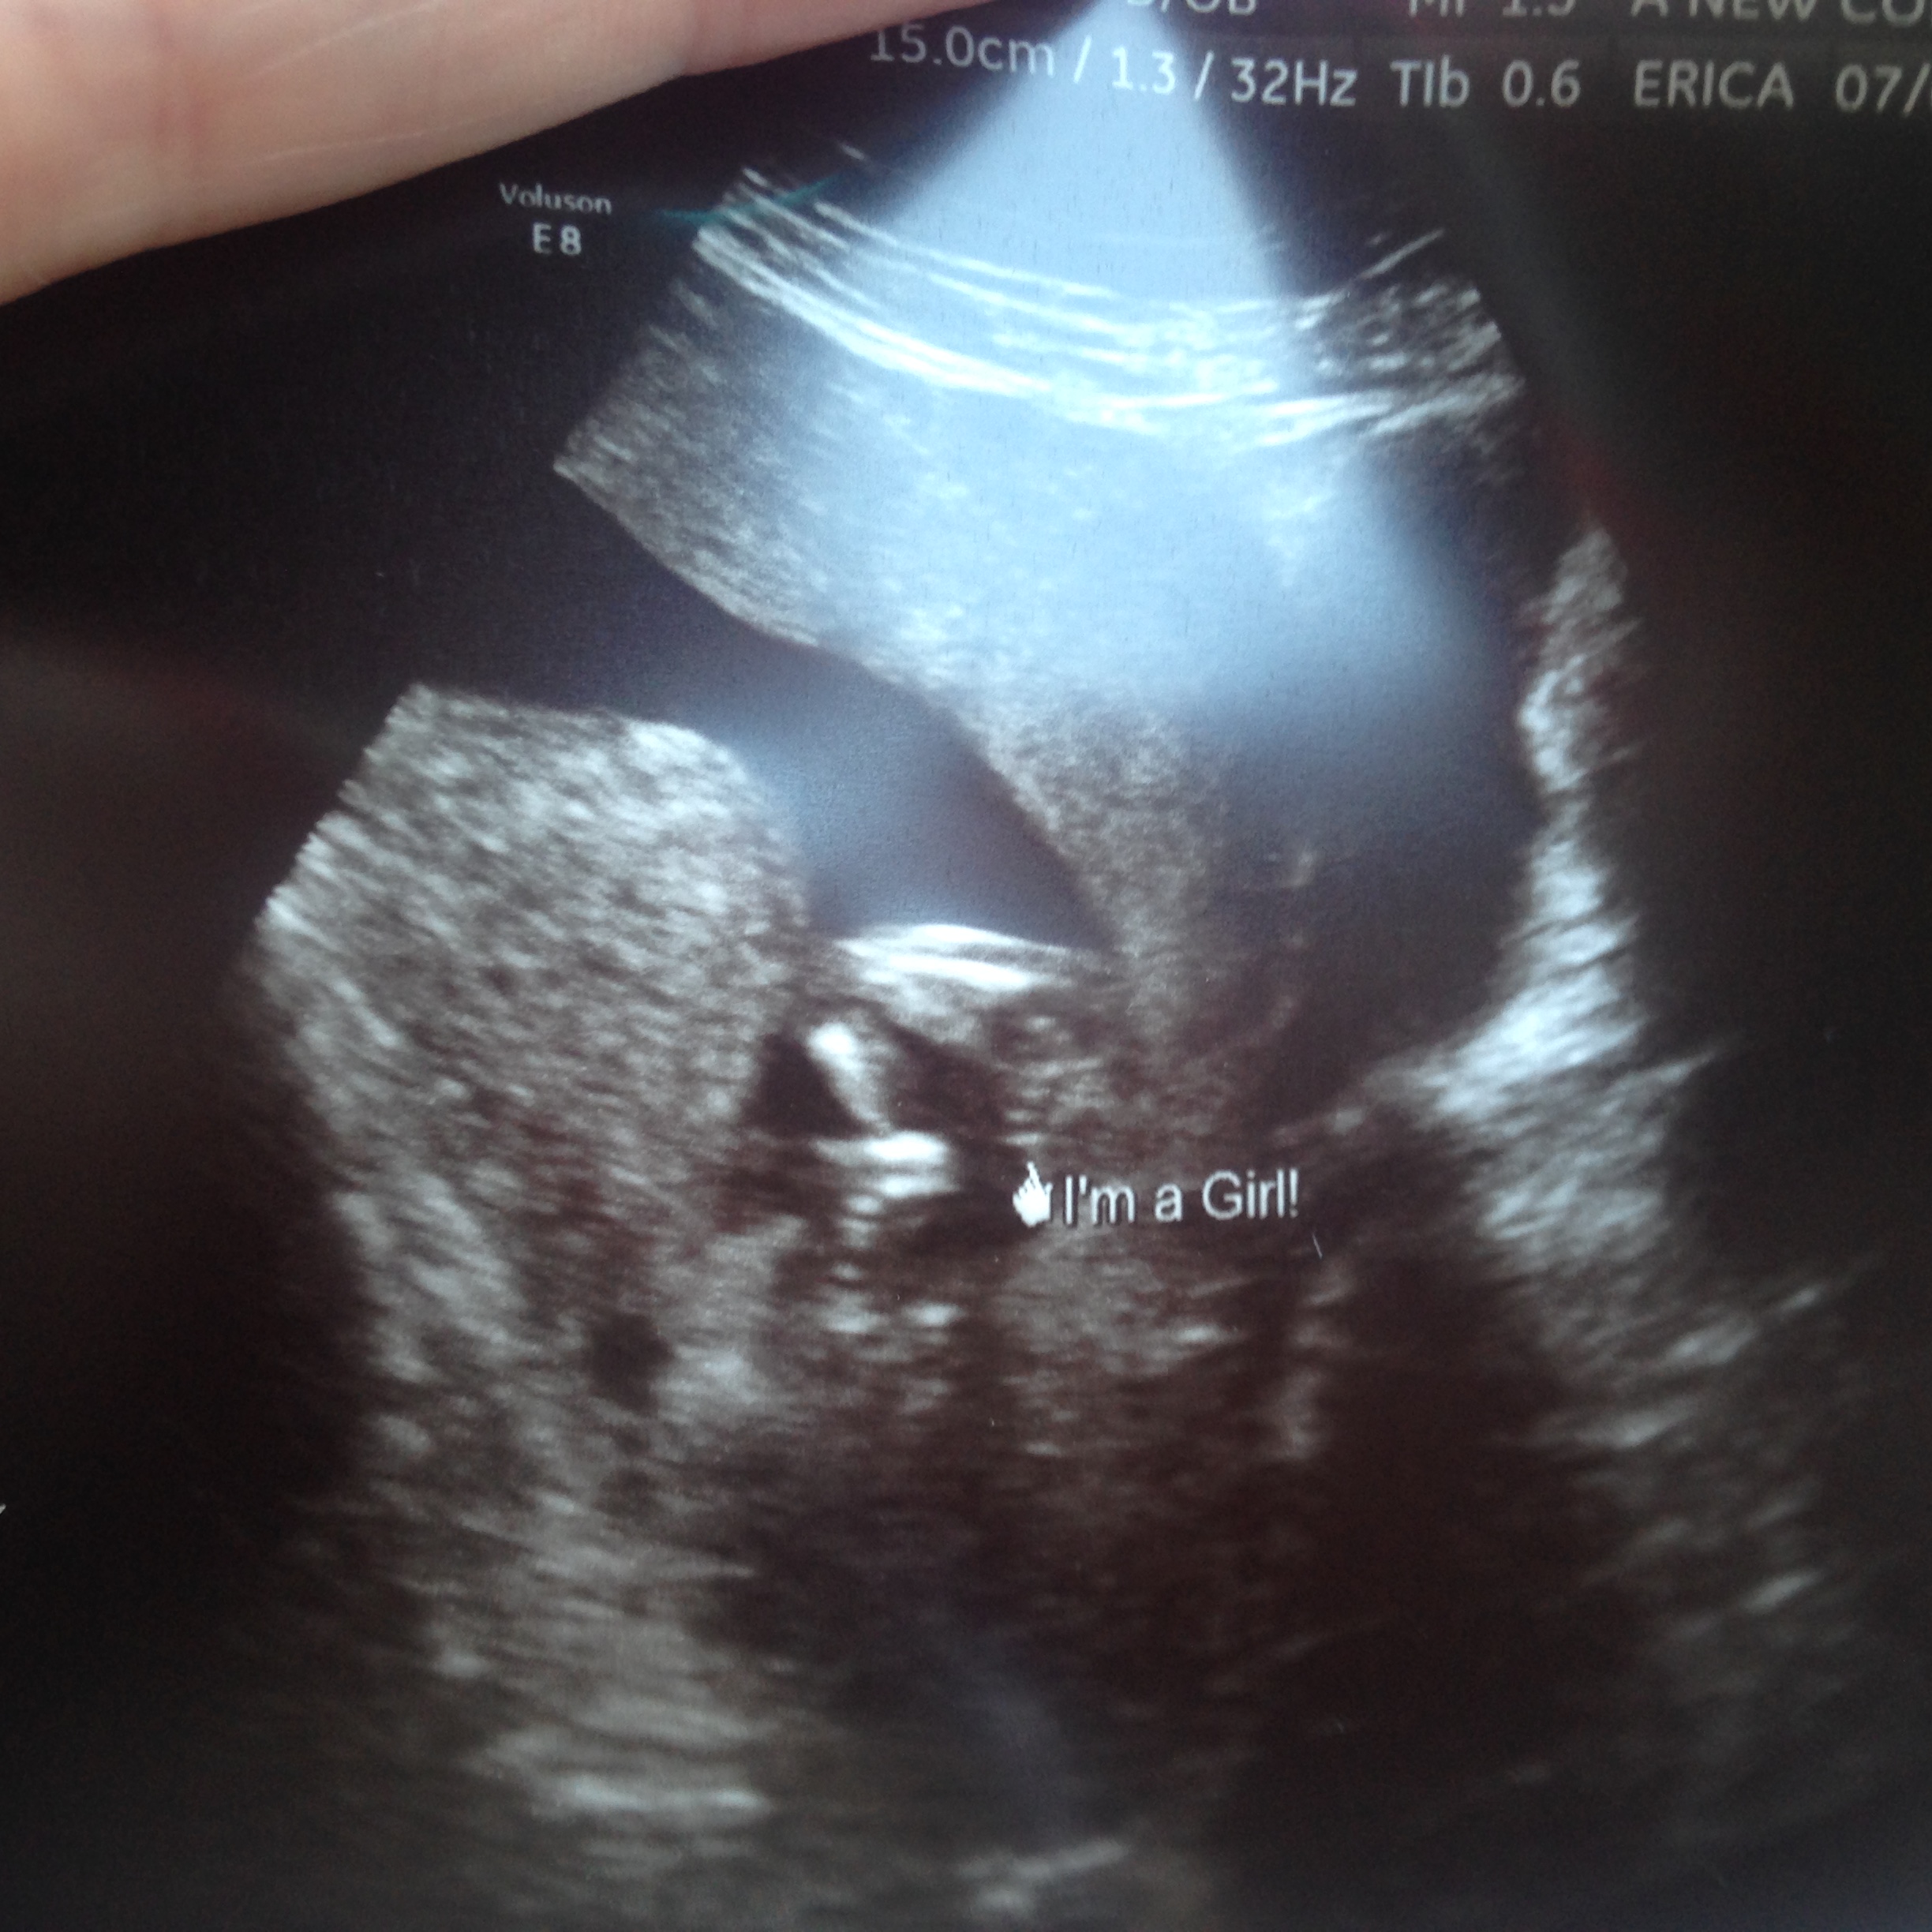

Had an elective ultrasound today at 14.3 weeks. Baby wouldn't completely open legs and the cord was between the legs. Ultrasound tech said she's guessing girl. Is this a def girl?Attachment 32065Attachment 32065

yes girl. three lines.

I think 14 weeks is too early for reliable potty shot.